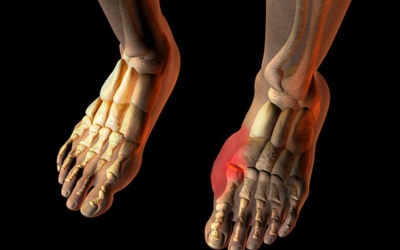

족저근막염은 여러가지 원인으로 발생할 수 있기 때문에 정확한 원인을 파악하고 적절한 치료를 받는 것이 중요해요. 구조적으로 평평한 발을 가지거나 정상보다 높은 아치를 가진 사람들은 족저근막염이 발병할 가능성이 더 큽니다. 다리 길이의 차이나 발 형태의 해부학적 이상도 족저근막염에 걸리기 쉽습니다.

주요 증상은 통증으로 발뒤꿈치 안쪽이 아주 아프며, 맨발로 바닥을 걸을 때 걸음을 내딛을 때마다 통증이 있어요. 가장 심한 통증은 아침에 일어나 첫 걸음을 뗄 때인데, 밤에 족저근막이 수축하다가 발에 체중이 가해지면서 갑자기 늘어나는 현상입니다.